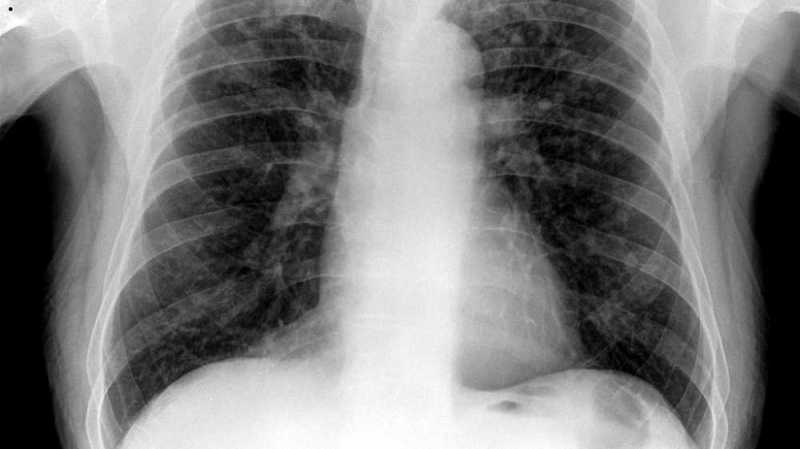

चुनावी साल में पहले भले ही जिला प्रशासन ने खनिज ट्रस्ट की राशि बांटने में भले जल्दबाजी दिखाई, लेकिन जो असली हकदार थे, उन्हें सहायता नहीं दी जा सकी। अब चुनाव आचार संहिता प्रभावी होने से भुगतान पर रोक लग गई है। खदानों में पत्थर फोड़कर सिलिकोसिस बीमारी से ग्रसित होकर कई मरीज उपचार के दौरान दुनिया छोड़ गए।

हालांकि मजदूरों की फिक्र का जिक्र हर जगह किया जाता रहा लेकिन, नियमानुसार मृतकों के परिजनों को तीन-तीन लाख रुपए नहीं दिए जा सके। इसके लिए डिस्ट्रिक मिनरल फाउंडेशन ट्रस्ट (डीएमएफटी) से भुगतान करना होता है। सिलिकोसिस मरीजों को उपचार के लिए एक लाख रुपए की सहायता दी जाती है। मरीज की मौत होने पर उसके परिजनों को तीन लाख रुपए और दिए जाते हैं। जिले में बिजौलियां व मांडलगढ़ क्षेत्र के 48 मरीजों को तीन-तीन लाख रुपए देने थे।